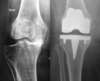

The primary total knee replacement consists of replacing the articular surfaces of the knee joint for the first time, which is in a knee that has never been implanted before the index operation. This is sort of a resurfacing concerning the femoro-tibial joint and, more inconstantly, the patello femoral joint.